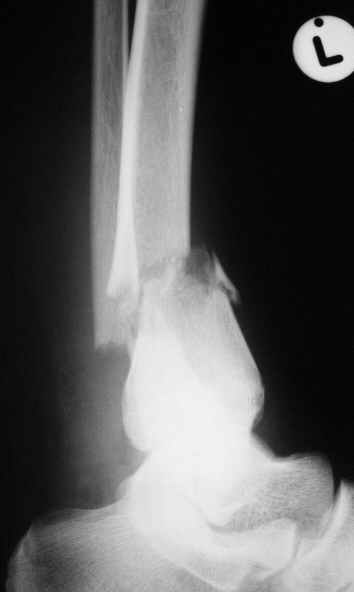

дистальный тиб.фиб. перелом |

Больной 17 лет , 3 недели с момента травмы, был переведен в наше отделение из соседнего

госпиталя.

Попытка закрытой ручной репозиции, предпринятая ранее в этой больнице,оказалась безуспешной, что и явилось причиной перевода к нам.

Чтобы вы предложили в данной ситуации?

Показана ли фиксация перелома малоберцовой кости в данном случае или в этом нет необходимости?